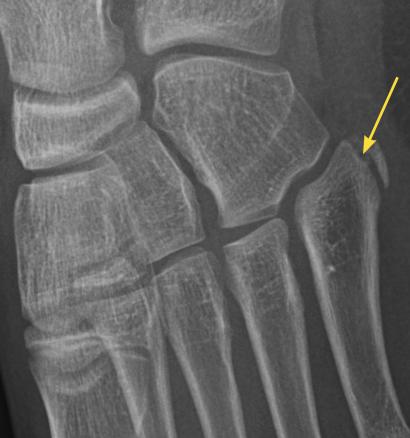

Radiographie du noyau épiphysaire de la base du cinquième métatarsien chez un enfant de 12 ans. Cette image n’est pas pathologique ; elle montre le cartilage de croissance vertical. En cas de fracture de la base du cinquième métatarsien, le trait est horizontal et la douleur bien localisée en regard.